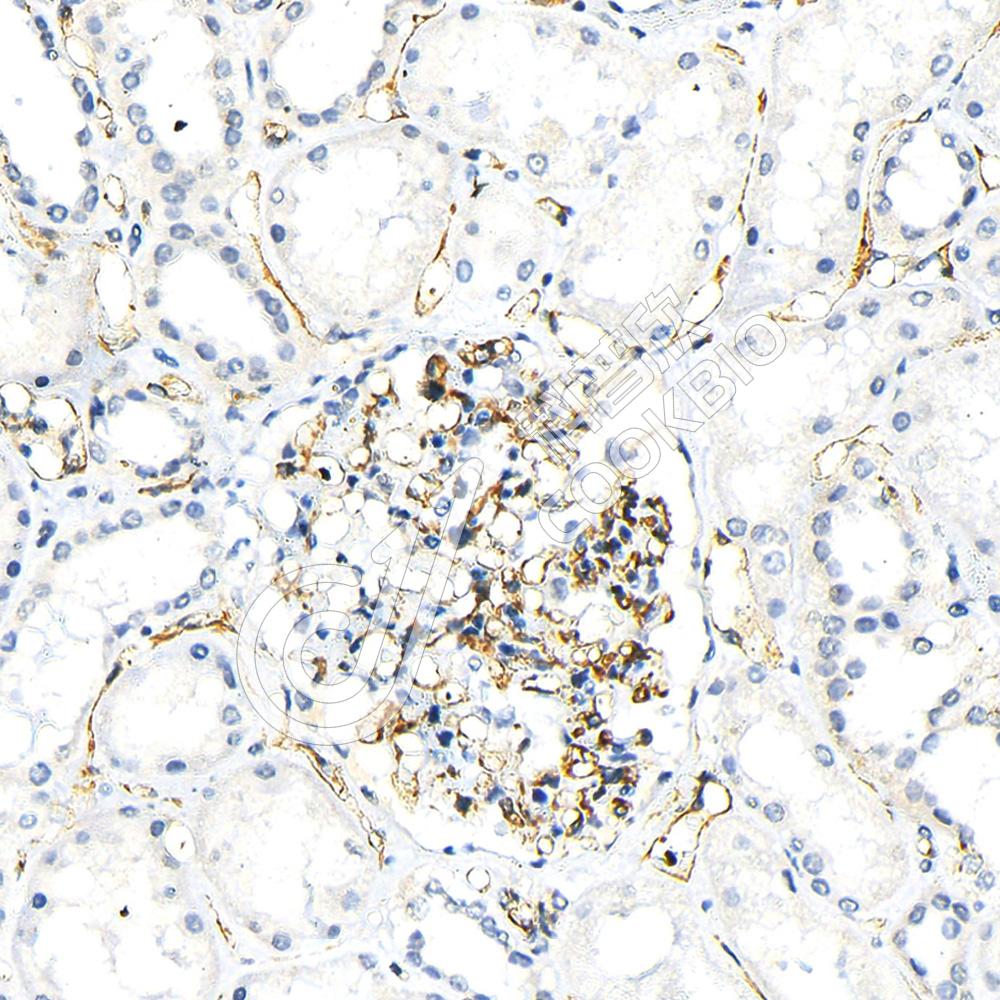

IHC检测CD34蛋白(货号 K5461394).

样品: 人肾, 4%多聚甲醛 (货号KSG1101) 固定12-24小时.

抗原修复: 柠檬酸抗原修复液(干粉, pH 6.0) (KSG1201), 高压锅均匀喷气计时2分钟.

—抗: 1: 800稀释, 4℃ 孵育过夜.

二抗: S-vision免疫组化多聚二抗(山羊抗兔),即用型 (货号KB3906), 室温孵育20分钟.